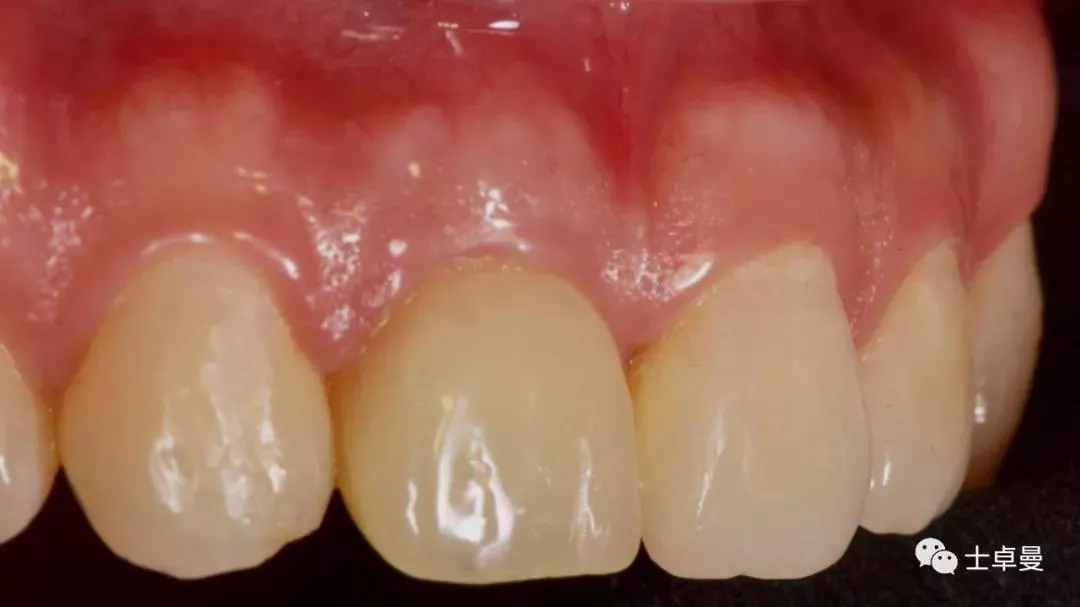

临时修复后2个月,龈缘及龈乳头位置理想,软组织健康

· 2个月后,见唇侧骨弓轮廓可,龈缘及龈乳头形态自然,去11临时修复体,植体ISQ值测定82,个性化取模,试戴Variobase氧化锆基台+LAVA氧化锆单冠,就位被动性良好,增加基台扭力至35Ncm,粘接固位上部冠,调合抛光。